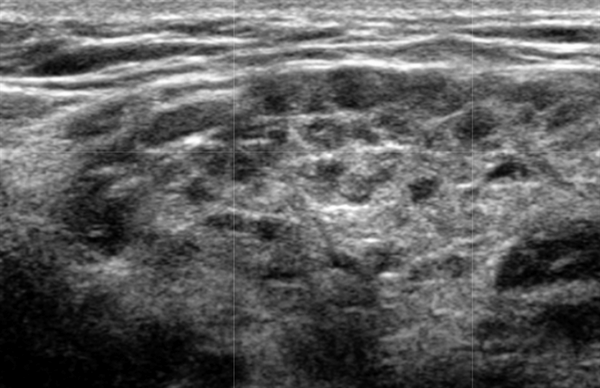

Результаты ультразвукового исследования слюнной железы при синдроме Шерена

Серошкальное УЗИ. Вовлеченность может казаться асимметричной. Ранние стадии «милиарных» кист (точечные кистозные изменения ≤ 1 мм) могут быть пропущены, однако их легко увидеть на УЗИ на более поздних стадиях. Диффузная железистая гипоэхогенность может быть только признаком раннего синдрома Шегрена, как и неоднородная паренхиматозная эхоструктура. Множественные дискретные гипоэхогенные очаги, разбросанные по слезным и слюнным железам. Солидные очаг представляют собой агрегаты лимфоцитов. Микроцисты возникают из-за деструкции ацинусов или расширения терминального протока из-за сжатия лимфоидными агрегатами. Макроцисты образуются из-за разрушения слюнной ткани. Гиперэхогенные полосы (фиброз) и кальцификаты обычно связанны с хроническим заболеванием. Система балльной оценки УЗИ (основанная на суммировании баллов по эхогенности паренхимы, однородности, наличию гипоэхогенных участков, гиперэхогенных отражений и четкости границ слюнных желез) хорошо коррелирует с результатами биопсии околоушной железы. Лимфоматозное изменение проявляется в виде доминирующего, нечеткого, твердого, гипоэхогенного образования в слюнных железах ± поражение лимфатических узлов.